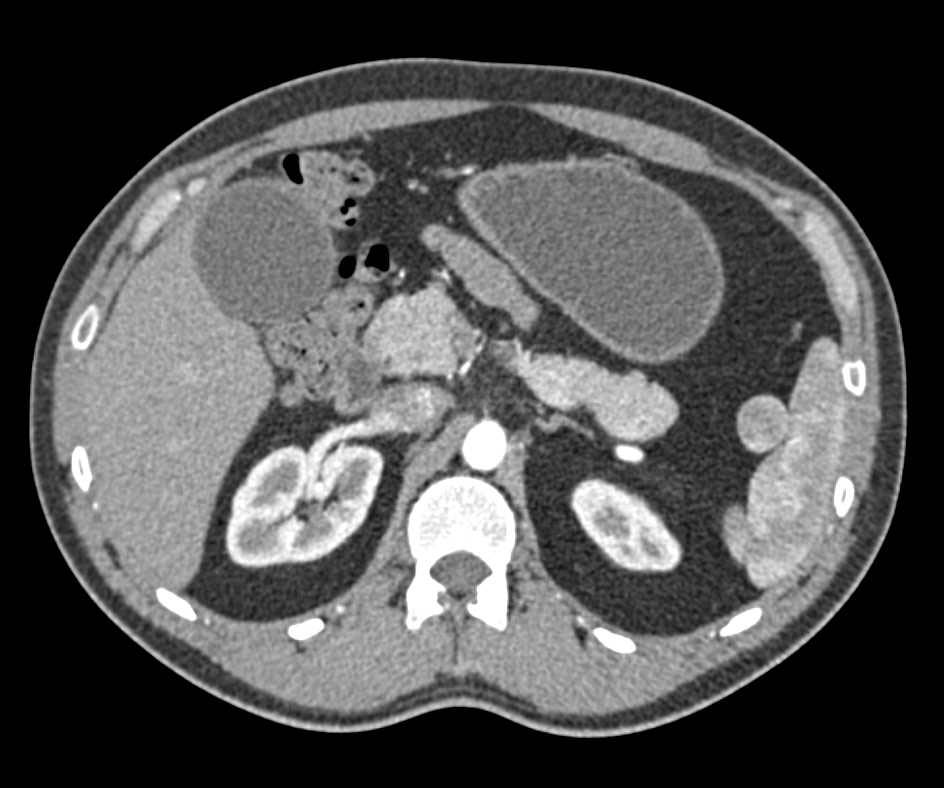

Carcinoma of the Tail of the Pancreas Involves the Spleen and Carcinomatosis